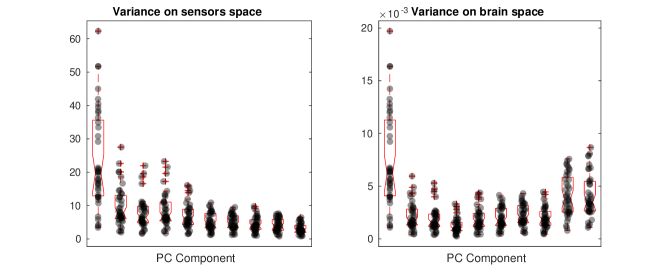

The second part of the analysis focuses on applying the proposed methodology to a multi-subject setting. Specifically, different subjects are considered. For each subject, the 6 minutes scan is used to compute a covariance matrix, resulting in covariance matrices . The template geometry in Figure 10 is used as a model of the brain space. Algorithm 2 is then applied to find the PC covariance functions on the template brain, associated with . We run the algorithm for iterations, and choose the regularizing parameter to be by inspecting the L-curve plot in the right panel of Figure B.2. The results for are shown in the appendices. The energy maps of the estimated functions , and and the associated first three covariance functions , and , are shown in Figure 13. High intensity areas, in yellow, indicate which areas present high average connectivity. In Figure 14, we show the subject-specific associated variances, both in the sensors space and the brain space.

The presented methodology opens up the possibility to understand population level variation in functional connectivity, and indeed, whether, just as we need different forward operators for individuals (due to anatomical differences), we should also be considering both population and subject-specific connectivity maps when analyzing connectivity networks. In fact, it is of interest to note that in both the single and multi-subject settings, the areas with high interconnectivity, displayed in yellow in Figure 11 and 13, seem to be at least partially overlapping with the brain’s default network (Buckner et al., 2008; Yeo et al., 2011). The brain’s default network consists of the brain regions known to have highly correlated hemodynamic activity (i.e. highest functional connectivity levels), and to be most active, when the subject is not performing any specific task. An image of the spatial configuration of the default network can be found, for instance, in Figure 2 of Buckner et al. (2008). From the plots of the associated variances in the sensors space (left panel of Figure 12 and Figure 14) we can see that these areas are also the ones that show high variability in connectivity across time or across subjects. This might suggest that the brain’s default network is also the brain region that shows among the highest levels of spontaneous variability in connectivity.

The plots of the variances on the brain space (right panel of Figure 14), when compared to those on the sensors space (left panel of Figure 14), demonstrate that these type of studies are highly sensitive to the choice of the regularization, not only in terms of spatial configuration of the results, but also in terms of estimated variances on the brain space. With a naive ‘first reconstruct and then analyze’ approach, where the reconstructed data on the brain space replace those observed on the sensors space, this issue could go unnoticed, as the variability that does not fit the chosen model is implicitly discarded in the reconstruction step and does not appear in the subsequent analysis. Also, importantly, our analysis deals with statistical samples that are entire covariances, overcoming the limitations of seed-based approaches, where prior spatial information is required to choose the seed. Seed locations are usually informed by fMRI studies and this comes with the risk of biasing the analysis when comparing electrophysiological networks (MEG) and hemodynamic networks (fMRI).